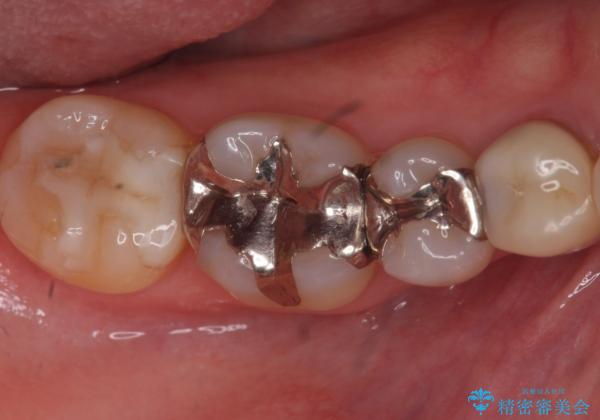

下の歯の銀歯が目立つ

- 口を開けた時、銀の詰め物が目立つとのことで来院。

銀の詰め物は歯質との間の隙間ができやすく

虫歯の再発リスクが高いです。